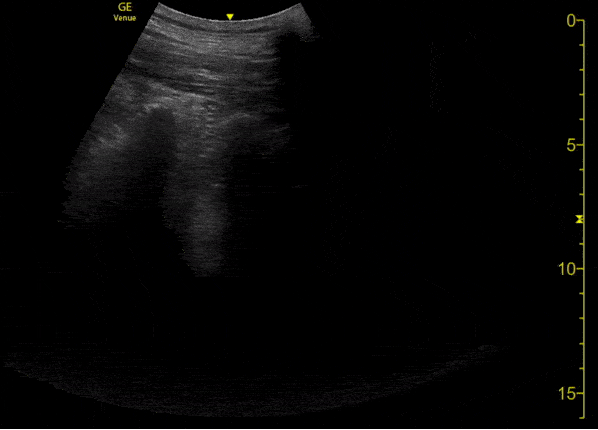

This is an ultrasound clip in a patient with confirmed COVID-19 pneumonia. The patient presented to the emergency department on day 3 of symptoms with fever. They were found to be tachypneic and with mild hypoxia. [Clip 2/3] Lung ultrasound demonstrates patchy B lines associated with thickening and irregularity of the pleural line. Image courtesy of Fritz Fuller (@POCUS_Society)